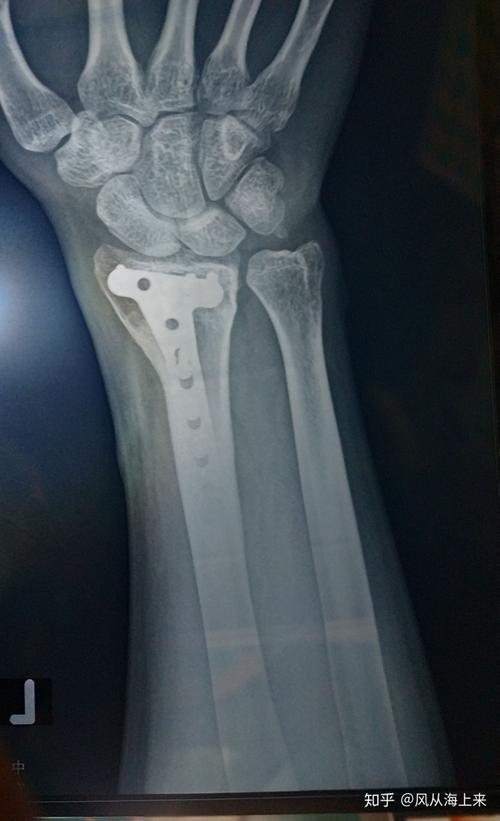

18岁 左桡骨远端粉碎性骨折累及关节面.做了钢板手术.

桡骨远端骨折

诊断:左桡骨远端陈旧性骨折 处理:手术治疗 case2 case3

左桡骨远端粉碎性骨折